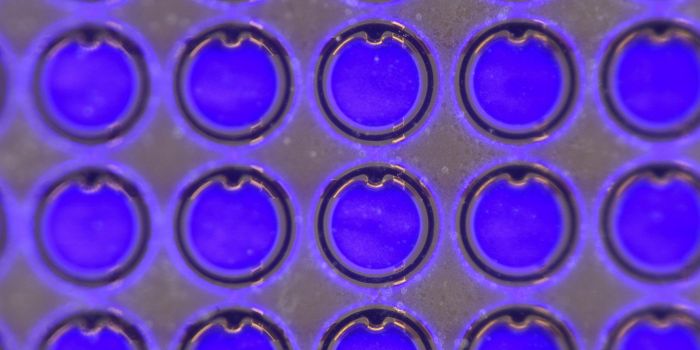

DEC 01, 2024Clinical & Molecular DXScientists have developed a new test that can easily and quickly identify bacteria in any liquid, such as water, milk, o ...